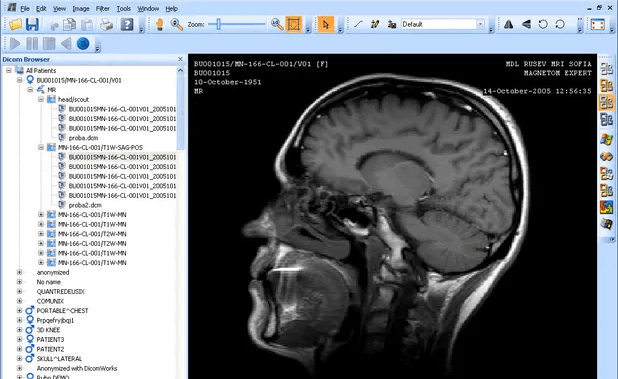

DICOM + PACS SERVER

The DICOM PACS Server is a medical imaging software designed to store, retrieve, and distribute medical images and associated data in compliance with the DICOM standard.

Our PACS Server provides a lightweight, open-source solution with features such as DICOM networking, anonymization, query/retrieve capabilities, and support for various medical imaging modalities like X-ray, MRI, CT scans, etc. It's highly customizable, scalable, and can be integrated with other healthcare IT systems, making it a popular choice for managing medical image archives.

DICOM PACS Servers/Clients Solutions are must for Big Hospitals or Radiology Diagnostic Imaging Centers. We are building Cloud based Radiology Diagnostic Imaging Centers.

Multi Modalities

Supports All Modalities

X-Ray, CT, MR, ULS, RF, PET, Dental, Fundus, OCT

Integration

- DICOM Viewer.

- Vol Rendering Plugin.

- Worklist Plugin.